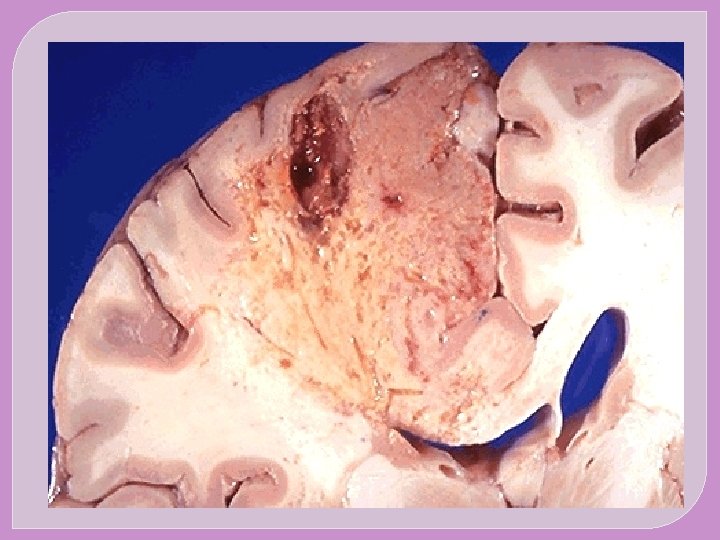

�The major sites for arteriolar embolization are �the lower extremities (75%) and �the brain (10%), �with the intestines, kidneys, and spleen affected to a lesser extent. �The consequences of embolization in a tissue depend on vulnerability to ischemia, caliber of the occluded vessel, and the collateral blood supply; �in general, arterial embolization causes infarction of the affected tissues.

SYSTEMIC EMBOLISM The origin of emboli: Most arise from intracardiac mural thrombi or from ulcerated atherosclerotic plaques The sequel: Arteriolar embolization (e. g. the brain, kidneys , spleen and intesrines)